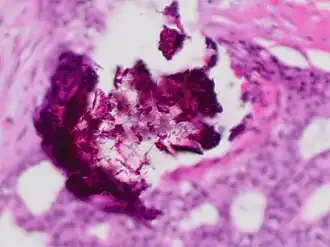

Histopathology of dystrophic calcium phosphate microcalcifications in ductal carcinoma in situ (DCIS) of the breast, H&E stain. -

In contrast to an artifact of crowded cells, the DCIS calcification pictured above characteristically extends outside the focal plane, as the background DCIS is blurred in this focus.